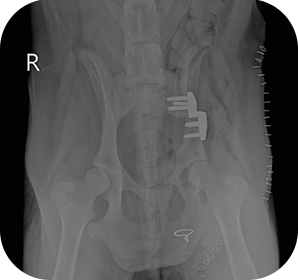

치료케이스

본동물의료센터의 치료사례를 소개합니다.